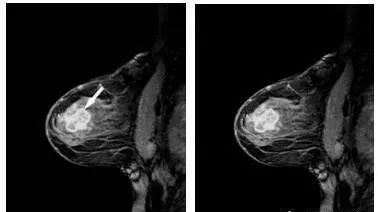

MRI乳腺高分辨成像:磁共振乳腺高分辨成像技术能够相较于钼靶机能够提供更舒适的检查环境,同时一次扫描,双侧成像,覆盖腋窝淋巴结。